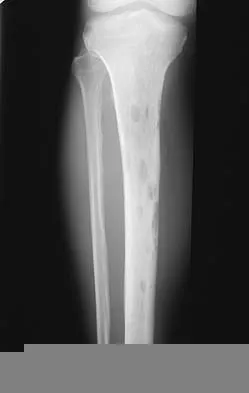

Orthopedic MCQs

Test your knowledge with updated Orthopedic MCQs for 2026. Perfect for board exam preparation, FRCS, and Prometric test practice.